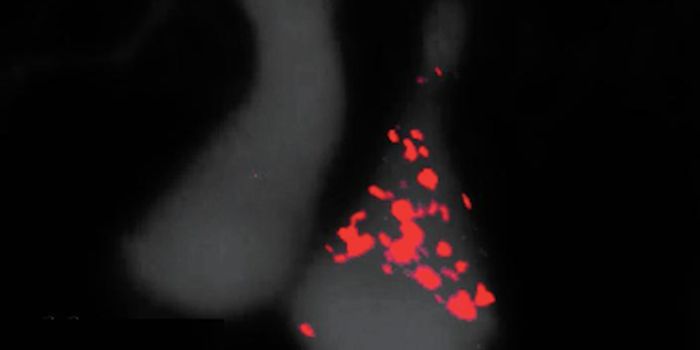

Read the latest articles about newly released neuroscience research and advances in experimental techniques. Topics include research news in neuroscience, neurology, psychology, brain science and cognitive sciences.